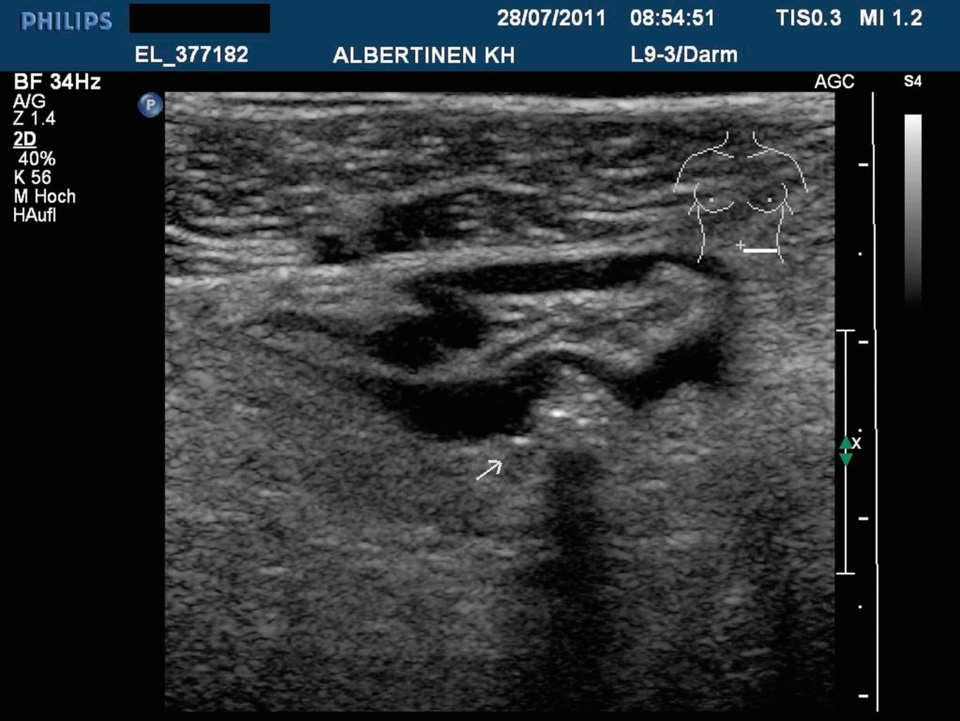

Divertikulitis mit gedeckter Perforation. Im umliegenden Fettgewebe sind Gas­bläschen zu erkennen (Pfeil). Sie erscheinen als echoreiche Reflexe. Divertikulitis mit gedeckter Perforation. Im umliegenden Fettgewebe sind Gas­bläschen zu erkennen (Pfeil). Sie erscheinen als echoreiche Reflexe. © Albertinen-Krankenhaus Hamburg/sonographiebilder.de